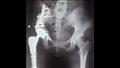

نجح فريق طبي بقسم جراحة العظام بمستشفى أسيوط الجامعي، في إجراء أول جراحة من نوعها لاستئصال ورم من عظمة الإلية ومفصل الحوض لفتاة تبلغ من العمر الخامسة عشر وتركيب مفصل صناعي كامل للحوض.

وقال الدكتور عمرو السيد علي أستاذ جراحة العظام واستشاري الجراحات الميكروسكوبية بجامعة أسيوط، إن المريضة تبلغ من العمر 15 عامًا وكانت تعاني من وجود ورم في عظمة الآلية ومفصل الحوض؛ مشيرًا إلى إجراء العملية الجراحية على مرحلتين في إطار زمني 3 شهور لتجنب البتر.

وجرى في المرحلة الأولى إزالة الورم من عظمة الآلية ونقل الجزء العلوي من عظمة الفخذ لتحل محل عظمة الآلية.

وأوضح الدكتور محمد مهران أستاذ مساعد جراحة العظام واستشاري جراحات تغيير المفاصل الصناعية بجامعة أسيوط، أنه تم بعد إجراء الفحوصات الطبية تم تركيب مفصل صناعي كامل ذو مواصفات خاصة للحوض وذلك دون اللجوء لتثبيت المفصل ولتجنب البتر لهذا الطرف؛ مشيرًا إلى نجاح العملية واستقرار الحالة الصحية للمريضة وتمت متابعتها لحين عودة الحركة للمريضه للصورة الطبيعية.